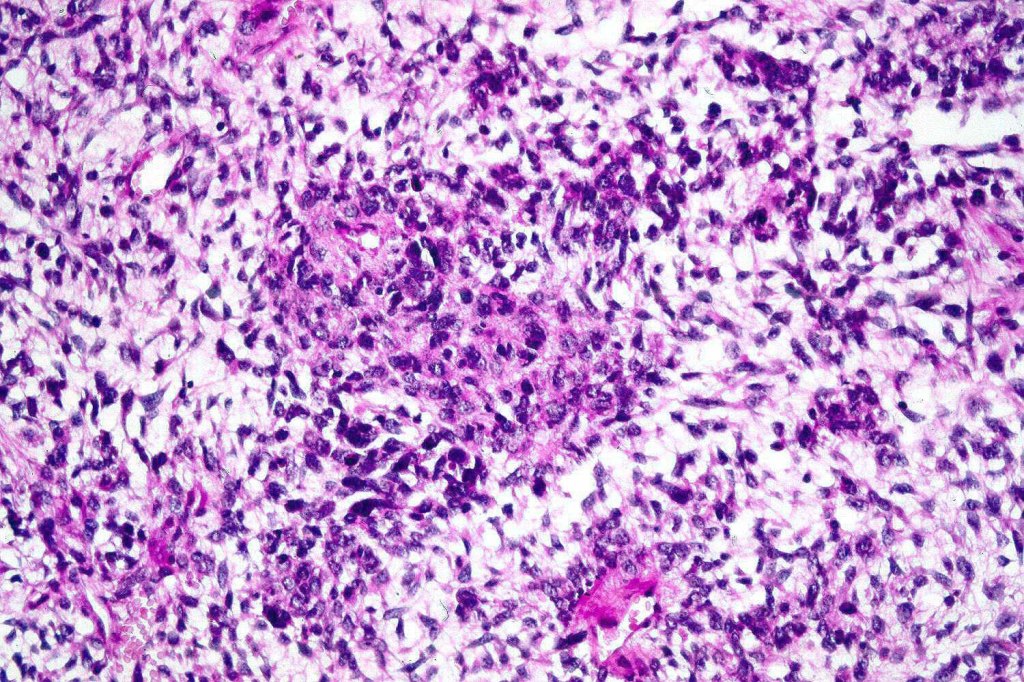

A rare variant of melanoma in which stromal cells produce excess acid mucopolysaccharides inprting a striking myxoid quality. The mucin is Alcian blue & colloidal iron positive, DPAS negative and the melanoma cells stain with typical markeres including S100 & HMB45. It may be seen in primary, recurrent or most often in metastatic lesions. The tumor cells are typically small although occcasionally they are epithelioid. Melanin is often sparse or even avsent making diagnosis difficult. In some examples, a pseudoglandular appearance is seen.

The differential diagnosis is very wide and can include numerous myxoid soft tissue tumors and epthelial mucin-secreting carcinomas. Diagnosis depends on clinical history, mucin stains and the judicious use of immunohistochemistry.